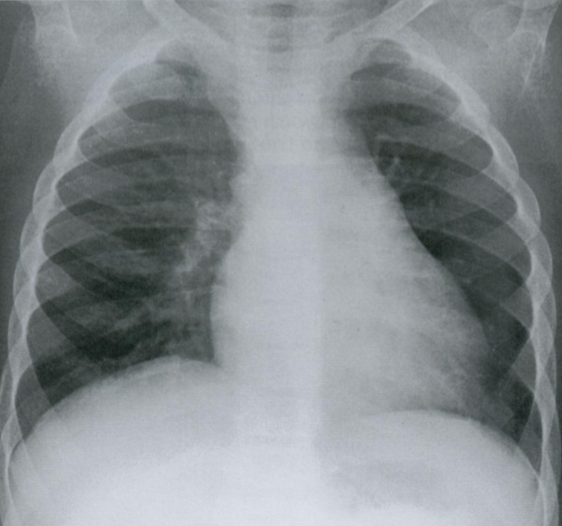

Оцените ассиметричность мягких тканей на снимке.

Обратите внимание на тень молочной железы (стрелочки), оцените симметричность теней слева и справа.

Ассиметрия прозрачности может наблюдаться после мастэктомий, радикального иссечения шейных лимфатических узлов, посттравматической гематомы грудной стенки, гепертрофии/атрофии мышц.

Пациентка после левосторонней мастэктомии с просветлением в нижних отделах с соотвествующей стороны (звездочка) в связи с отсутствием молочной железы (стрелочки).

Если есть сомнения, можно внимательнее рассмотреть подмышечную область на предмет возможного наличия металических клипс после иссечения ЛУ подмышечной впадины (фото ниже).

Ключевой момент - не ошибиться, принимая уменьшение прозрачности с одной стороны за выпот или внутрилегочное образование.